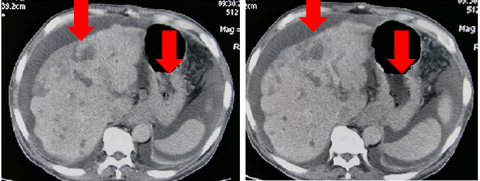

CT(外院2018.05):肝内多发占位,考虑转移;贲门胃底部溃疡性肿物;胃低及胃左动脉多发肿大淋巴结;考虑转移。

图表1-2:CT(外院2018.05)

2018-11-05加入S1单药化疗,6次靶向+2周期S1化疗后,肿瘤标记物下降:CEA 947ug/L → 23.5ug/L血常规恢复正常。肿瘤明显缩小,范围变少。ECOG 1分

图3

病灶缩小,疗效评价:PR